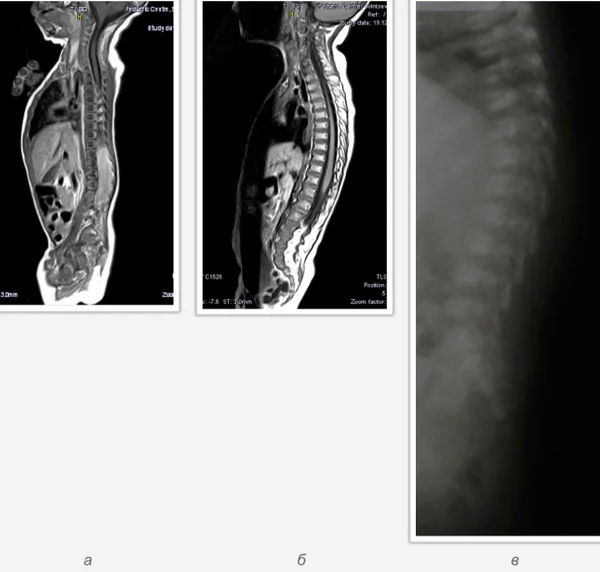

В качестве примера приведены 2 случая хирургического лечения новорожденных с врожденными опухолями головного мозга и позвоночного канала. У новорожденной девочки опухоль (хориодпапиллома) располагалась в области треугольника правого бокового желудочка (рис. 28 а, б). В возрасте 2-х недель жизни опухоль удалена. По данным МРТ головы с внутривенным введением контрастного препарата выполненной через 2 дня после операции опухоль удалена тотально (рис. 28 в). Послеоперационных осложнений не наблюдалось. У второго пациента 2-х нед. жизни врождённая опухоль (нейробластома) располагалась в позвоночном канале на уровне Th10-L3 позвонков (рис. 29 а) и распространялась в забрюшинное пространство. Клиническая картина заболевания складывалась из нижнего вялого парапареза и нарушения функции тазовых органов. Во время операции остистые отростки Th 11-L3 позвонков рассечены по средней линии. Дужки 6 данных позвонков надломлены и разведены в стороны. Опухоль располагалась экстрадурально, отделена от дорзальной поверхности дурального мешка и корешков спинно-мозговых нервов, после чего полностью удалена из позвоночного канала. Половинки дужек позвонков сведены к средней линии и сшиты между собой. Опухолевый узел в забрюшинном пространстве через 2 нед. удален онкологами. Через год после операции по данным МРТ рецидива опухоли нет (рис. 29 б). При спондилографии дефектов задней стенки и деформаций позвоночника не выявлено (рис. 29 в). Мальчик ходит, мочу и кал удерживает.